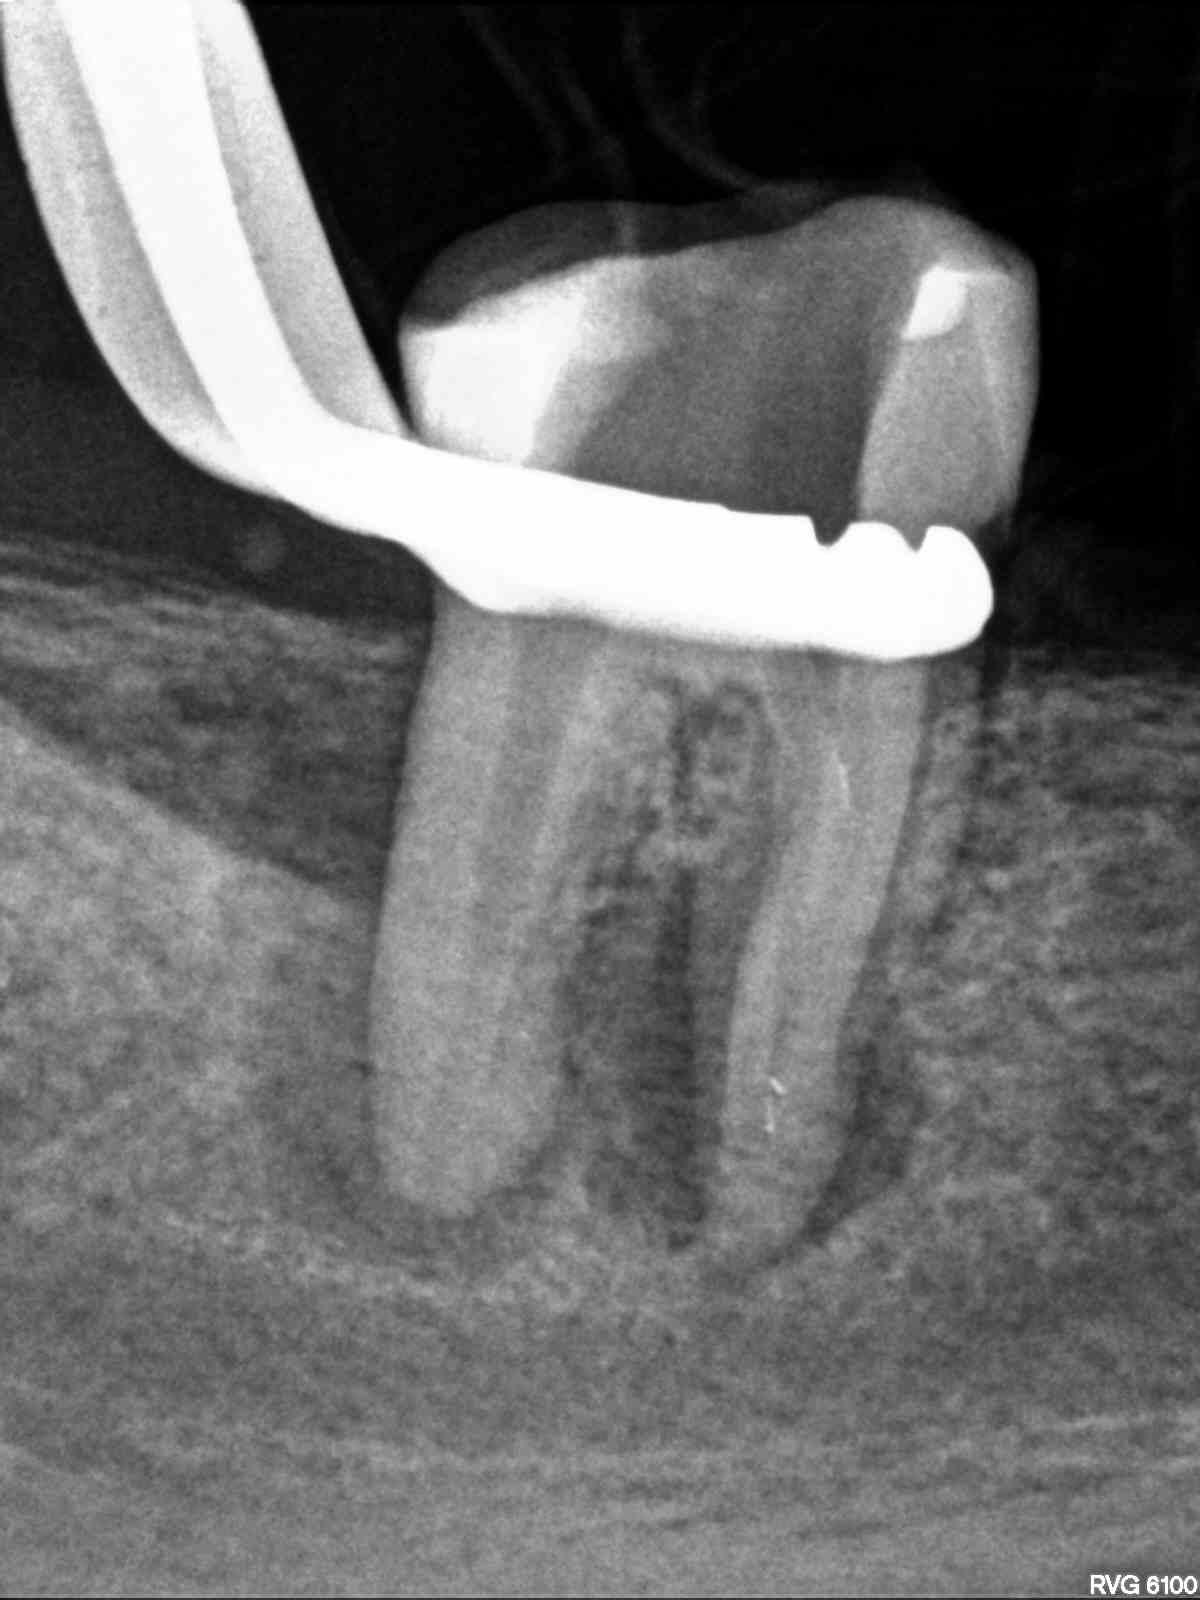

R5

1200 × 1600

Fragmententfernung